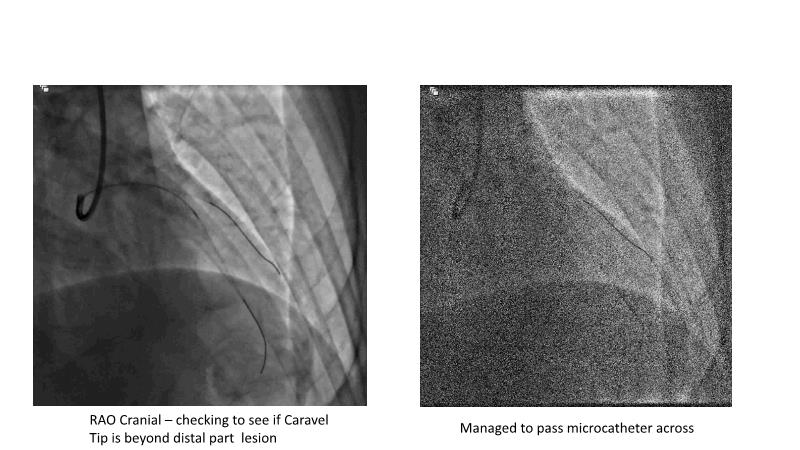

This session is recommended for you if you are seeking insights into the advantages of using IVUS imaging over visual assessment for better outcomes in left main bifurcation procedures. Discuss with experts the benefits of using RotaCUT in lesion preparation for left main bifurcation and explore the impact of high radial strength stents on the procedure's success.

• To understand why the use of IVUS imaging is different from seeing with experienced eyes to achieve improved left main bifurcation outcome